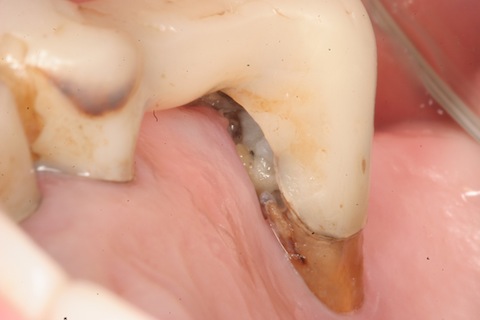

80代女性、左上6、歯根分岐部の歯根面カリエスによる歯根分離。最近こういう症例が多いように思います。歯周病の長期管理をしているとどうしても歯根分岐部より歯槽骨が下がってしまった症例も手がけますので、仕方がありません。他にも何症例かアップしようと思っています。痛みはないものの、DH(デンタルハイジニスト:歯科衛生士)が歯根分岐部に食渣がたまって、虫歯になっているようだと報告があった症例です。ちょっと開けてみましたが、歯根分岐部内部は広範囲な虫歯になっています。分岐部は酸素濃度が相対的に低いので、酸素濃度差腐食が起こりやすい環境です。もちろん食渣は溜まるので、発酵による酸性環境ですから、電気化学的な腐食を止める事は難しいのです。口蓋根はすでに抜けていました。頬側根の内側だけをCR充填して、とりあえず抜歯は先送りです。